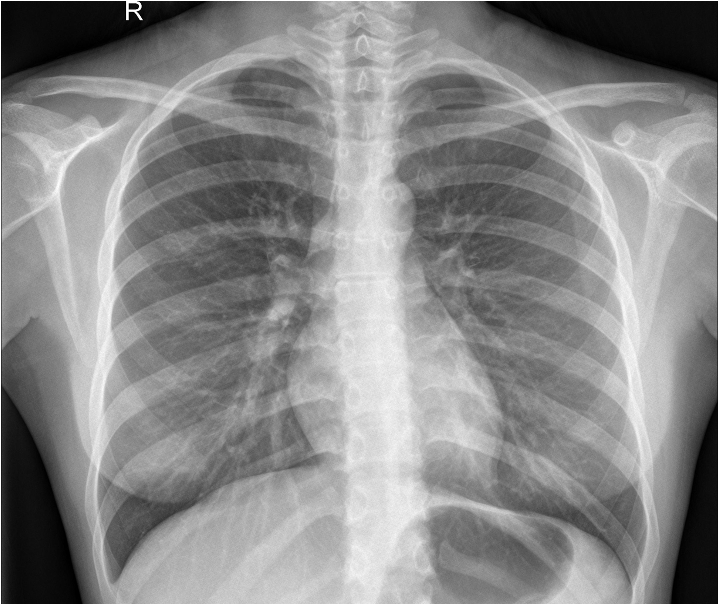

Figure 2 exemplifies two healthy lungs (upper two) and two lungs suffering from pneumonia (lower two). All images of the data set are recorded with different resolutions. Therefore, we convert the images to greyscale and compress them to 128128 pixels. We allocate 1,500 images to the training set, 200 to the validation set, and 1,400 to the test set.